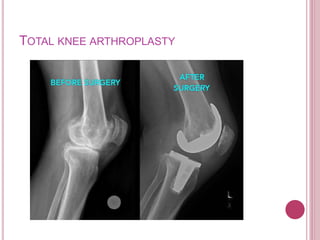

TOTAL KNEE ARTHROPLASTY